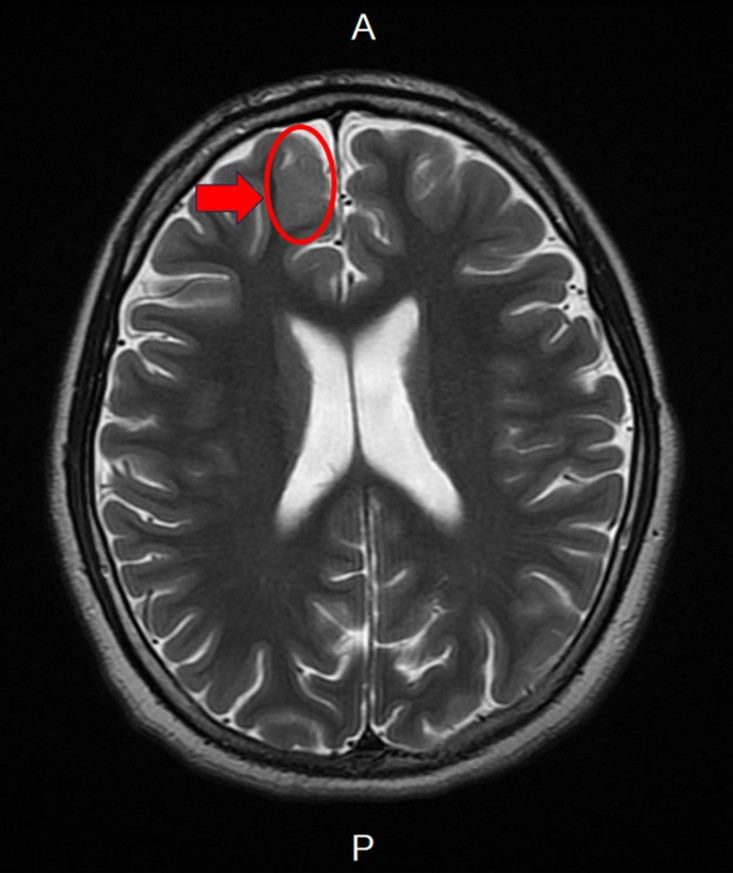

新竹臺大分院小兒部張寶玲醫師評估後發現,男孩腦波檢查出現頻繁右側額葉局部癲癇波,懷疑可能存在腦部病灶。進一步安排腦部磁振造影檢查後,發現右側額葉異常病灶。由於病人屬於頑固性癲癇,在多種抗癲癇藥物治療下仍持續發作,醫療團隊評估後建議接受癲癇手術。

手術過程中透過腦皮質腦波監測,由張寶玲醫師即時判讀並定位癲癇來源,再由神經外科醫師切除病灶。術後病理報告證實為局部腦皮質發育不良(Focal Cortical Dysplasia)。男孩術後恢復良好,未出現併發症,也未再發生意識喪失,癲癇發作次數明顯減少。